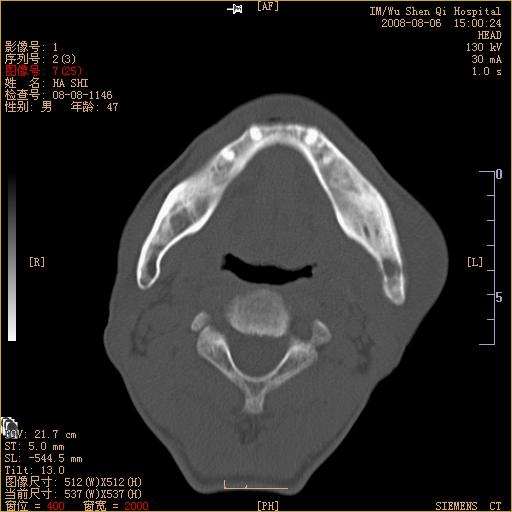

标题: CT15051:男 47岁 左下颌角部肿痛一周 [打印本页]

标题: CT15051:男 47岁 左下颌角部肿痛一周

骨质破坏,无硬化边,周围软组织肿胀,占位

考虑为:1.左侧下颌骨骨髓炎。2.左侧下颌骨放射性骨坏死?(不知是否相关病史)

牙源性骨髓炎可能

左下颌骨感染性病变,牙源性可能。

左侧下颌智齿阻生。

考虑左下颌骨骨髓炎。